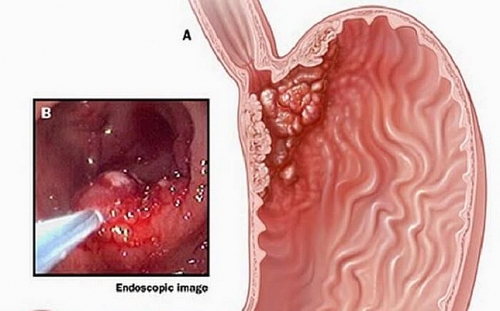

Xét nghiệm máu có phát hiện ung thư dạ dày không?

Xét nghiệm máu có phát hiện ung thư dạ dày không là điều nhiều người thắc mắc khi có dấu hiệu bệnh.

Các giai đoạn ung thư dạ dày

Các giai đoạn ung thư dạ dày gồm những gì? Có thể phòng tránh ung thư dạ dày bằng cách nào? Đọc bài viết ngay để nắm rõ thông tin.

Dấu hiệu ung thư dạ dày giai đoạn cuối

Dấu hiệu nào cho biết ung thư dạ dày đã tới giai đoạn cuối? Cần làm gì để phát hiện bệnh sớm?

Cắt ung thư dạ dày sống được bao lâu?

Nếu không may bị ung thư dạ dày, việc phải cắt bỏ một phần dạ dày có thể sẽ xảy ra nếu giai đoạn bệnh nặng. Vậy cắt ung thư dạ dày sống được bao lâu?

Triệu chứng ung thư dạ dày

Triệu chứng ung thư dạ dày gồm những triệu chứng gì? Cần làm gì để phát hiện sớm ung thư dạ dày?